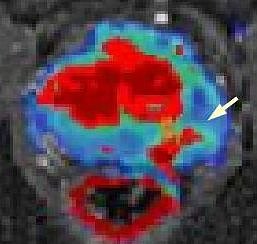

Prostata - Pfeil zeigt auf Karzinom (Foto: SHK) Prostata - Pfeil zeigt auf Karzinom (Foto: SHK) Mitarbeiter des radiologischen Institutes im Nordhäuser Südharz-Krankenhaus werden zusammen mit Privatdozent Dr. med. Ansgar Malich vom 26. November bis zum 1. Dezember am größten radiologischen Kongress der Welt in Chicago teilnehmen. Bei diesem Jahrestreffen der nordamerikanische Röntgengesellschaft, an dem 65.000 Fachleute teilnehmen, wird der Nordhäuser Mediziner über die MR-gestützte Abklärung von auffälligen Befunden an der Prostata referieren. Das Nordhäuser Krankenhaus ist eines von sehr wenigen Häusern in Deutschland und bislang das einzige in Thüringen, das diese interventionelle Methode anbietet. In diesem Zusammenhang besteht seit längerem eine enge Zusammenarbeit mit dem Fraunhofer-Institut in Bremen.

Wenn bei einem Tumorverdacht die ultraschallgestützte Biopsie der Prostata keinen Tumornachweis erbringt, kann die MRT-basierte Biopsie als zweite Option angewandt werden. Der Vortrag befaßt sich mit den nötigen Vorbereitungen und der benötigten Hardware, der Planung der Biopsie, der Durchführung, möglichen Komplikationen und den histologischen Ergebnissen im Vergleich zu den ursprünglichen Bildcharakteristika im MRT.

Hierbei hat sich eine Kooperation mit niedergelassenen urologischen Kollegen in Nordthüringen und Sachsen-Anhalt herausgebildet, die folgerichtig auch Koautoren dieses Vortrags sind. Die MR-gestützte Biopsie ist vom Nordhäuser radiologischen Team inzwischen bei mehr als 50 Patienten im Südharz-Krankenhaus bereits erfolgreich angewandt worden und daraus konnten Erkenntnisse für die weitere Arbeit gewonnen werden, die nun vorgestellt werden.